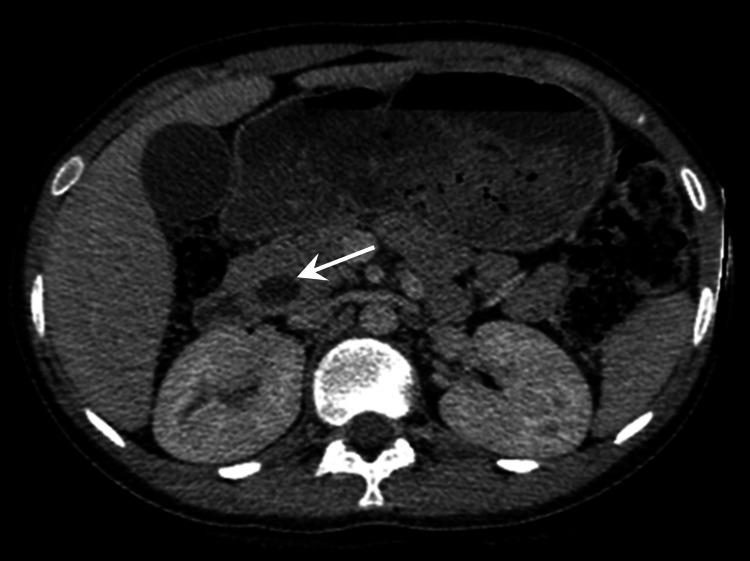

Periampullary carcinoma in adolescents is very rare and may be associated with hereditary syndromes. Pancreaticoduodenectomy (PD) in adolescents is rarely performed. The experience and results of pancreaticoduodenectomy in adolescents are not well reported. Here, we report a case of periampullary carcinoma, duodenal origin, signet ring type with microsatellite instability (MSI), in a 13-year-old male for which pancreaticoduodenectomy was successfully done.

青少年壶腹周围癌非常罕见,可能与遗传综合征有关。青少年很少进行胰十二指肠切除术(PD)。关于青少年胰十二指肠切除术的经验和结果报道较少。在此,我们报告一例13岁男性十二指肠起源的印戒型壶腹周围癌伴微卫星不稳定性(MSI),该患者成功接受了胰十二指肠切除术。